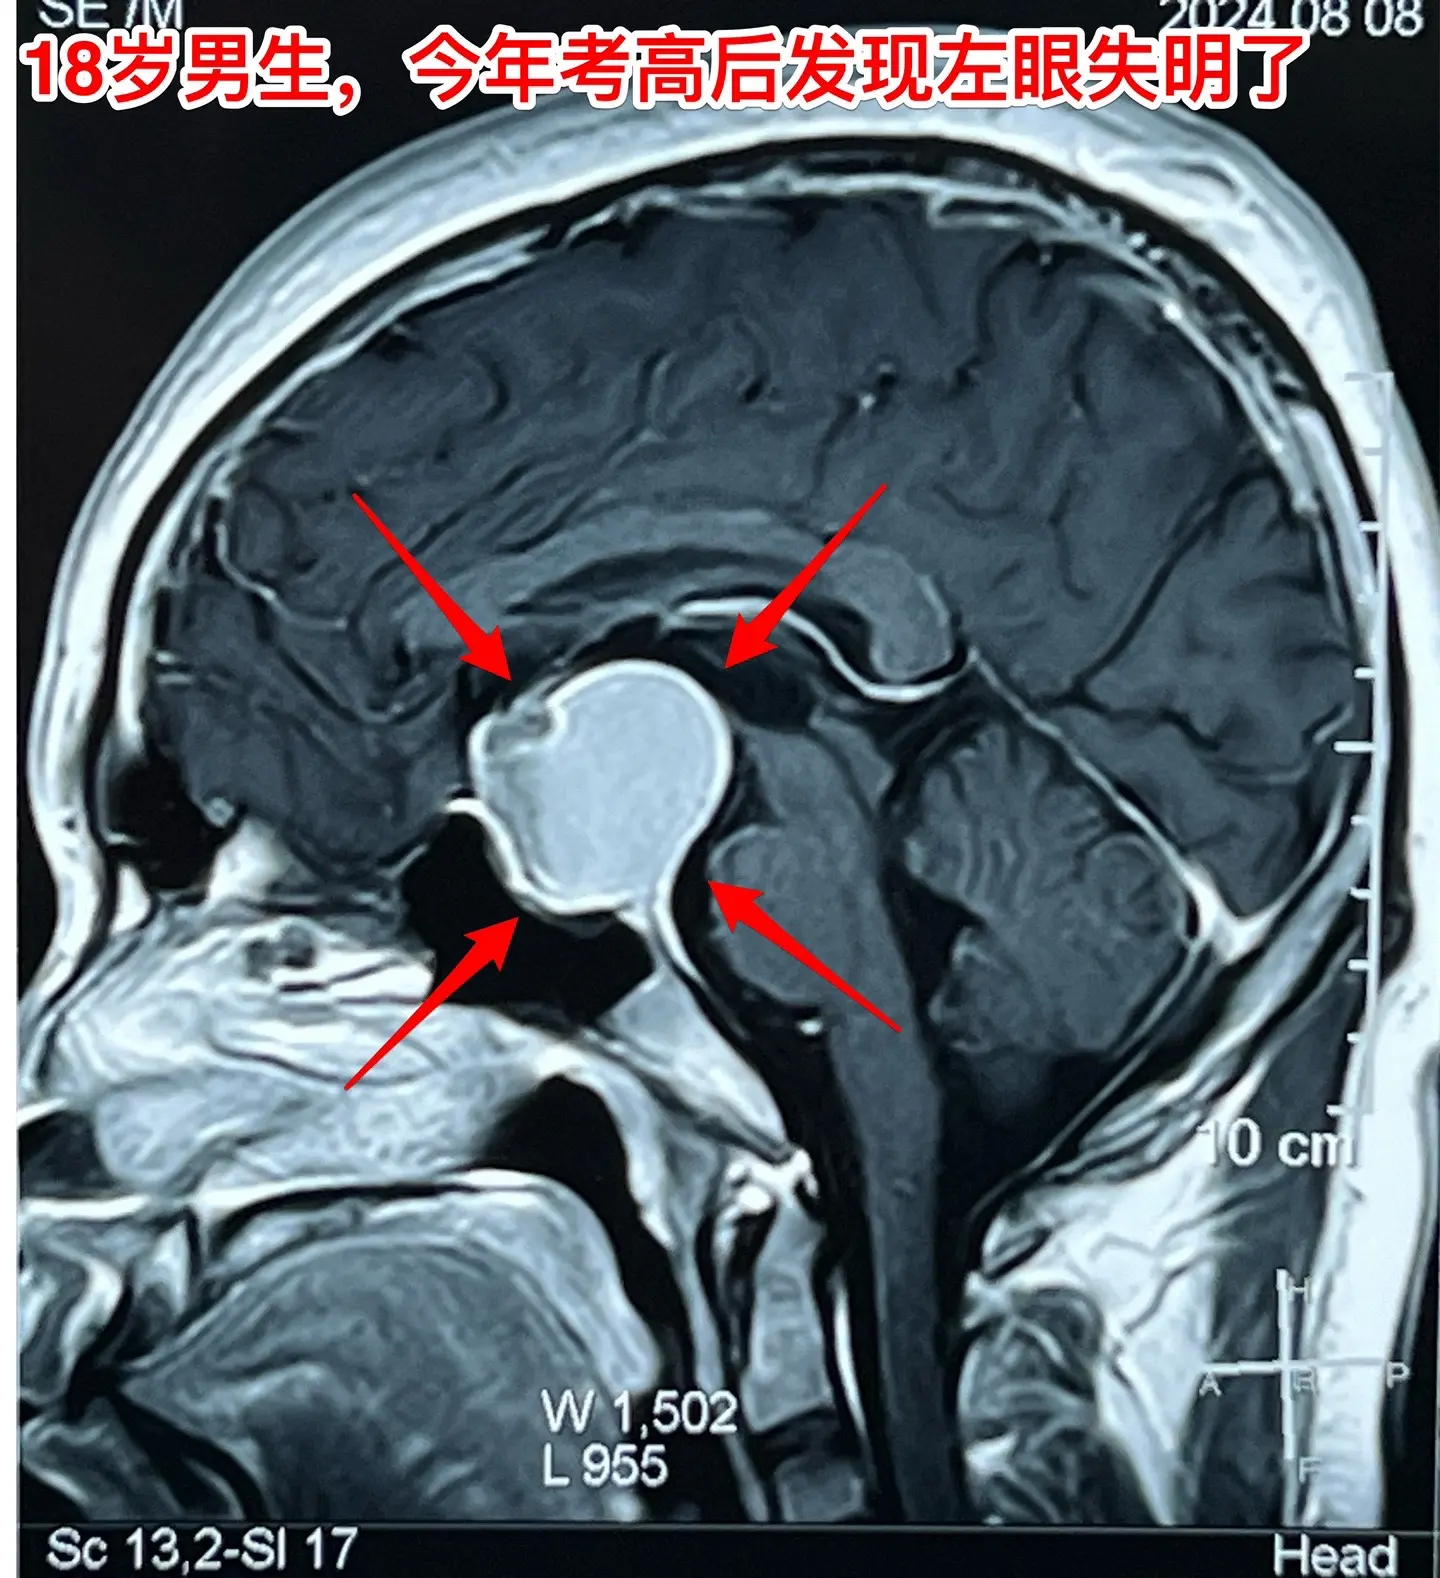

男生高考后想打工,居然发现脑部长瘤了。18岁四川男生,高考后到北京来投奔姑姑,准备到北京打工。 小伙子命苦啊,幼时父亲因病离世,母亲离家,他和奶奶一起生活、长大。 高考后小伙子到北京来投奔姑姑,准备打工,姑姑已经在北京安家了。 姑姑发现小孩子的眼睛似乎出了问题,视力不好,看手机比较困难。仔细询问,才知道他的左眼已经失明了差不多三个月了,一年多前他的右眼视力也明显下降了,这个粗心的孩子居然没有告诉家人。 到北京的医院检查,发现脑部长瘤了,见图。真是祸不单行!瘤体积不小了,小孩子除了视力差之外,精神也差。八月份住院准备做手术,作化验发现尿糖四个+,血转氨酶很高、胆红素也高。用药治疗了一段时间化验值才有好转。 直到九月二号才作手术。手术中发现这个病灶没有钙化,不是典型的颅咽管瘤。很幸运的是病灶完全切除了,而且垂体和垂体柄、下丘脑均保护完好。